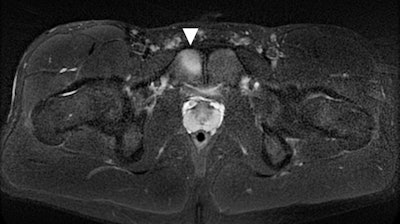

Two reading radiologists identified 42 bone stress injuries in 29 athletes: four stress fractures and 38 stress reactions. All 29 competitors had MRI exams and seven had x-ray exams; almost three-quarters (72%) had signs of injury before they arrived at the Games.

Adachi and colleagues discovered that bone stress injuries were most common in women (55%), in the lower extremities (66%), and in track and field players (45%). Of those athletes found to have bone injuries before checking into Olympic Village, 21% did not start or finish their events.